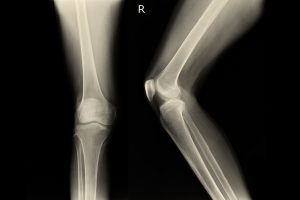

Chirurgia protesica. Artroscopia di ginocchio. Infiltrazioni intraarticolari rigenerative. Cellule mesenchimali. Lesioni legamenti ginocchio. Traumatologia dello sport.